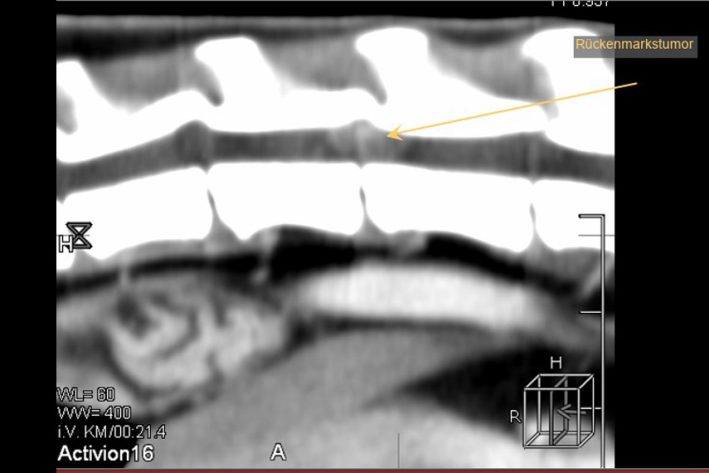

Rückenmarkstumor (Meningeom)

Rückenmarkstumor (Meningeom). Am Übergang der Brust- zur Lendenwirbelsäule

CT 3D-Rektonstruktion nach Laminektomie und Entfernung des Rückenmarkstumors